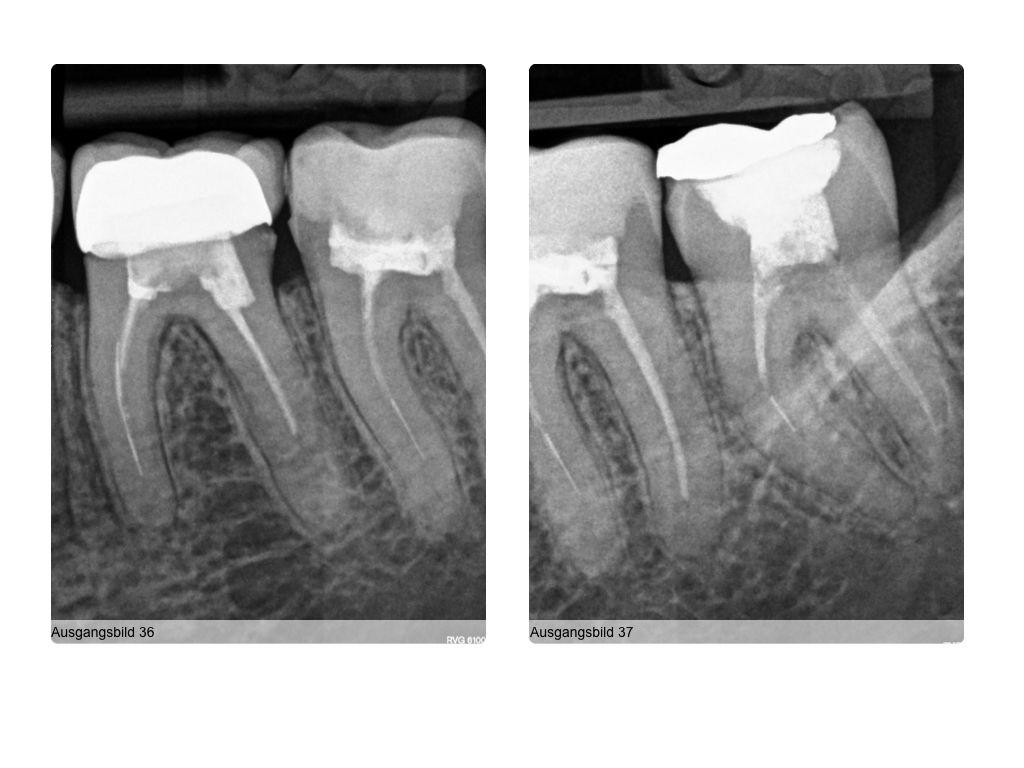

4 auf einen Streich